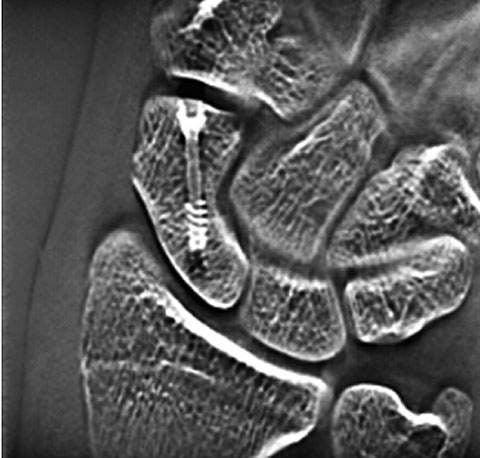

Consequently, to minimize artifacts in tomosynthesis of the scaphoid bone, this hospital positions the screw axis parallel with both the tube scanning direction and the tabletop and uses 40° tomosynthesis angle. The image reconstruction slice thickness parameter was set to the minimum thickness (–) to set a 1mm slice pitch. Fig. 8 shows an actual tomosynthesis image of the scaphoid bone. The black artifact band apparent along the length of the screw does not affect on the evaluation of bone union at the margins of the scaphoid bone. As tomosynthesis permits the evaluation of screw fixation of the scaphoid bone, we do not currently conduct stress radiography.

Case 4 – 15-year-old male: injured right hand in a fall from a bicycle and visited our hospital one month later, after diagnosis of fracture of the scaphoid bone at another hospital. Tomosynthesis performed on arrival at the hospital confirmed a bone defect in the scaphoid waist. A bone graft with screw fixation and cast immobilization was performed two months after the injury. The fracture line in the scaphoid bone has become indistinct in the tomosynthesis image taken in the 16th week. This is assumed to result from progress of bone union (Fig. 13).